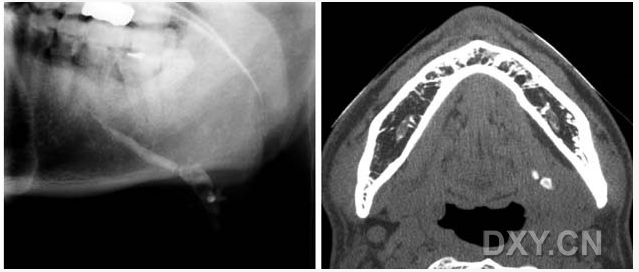

頜骨骨折